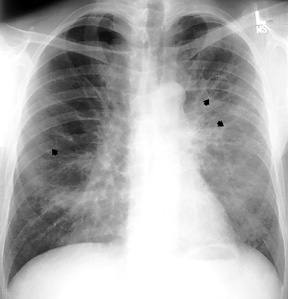

Common pulmonary infection in HIV patient

Dx?

Pathologic finding?